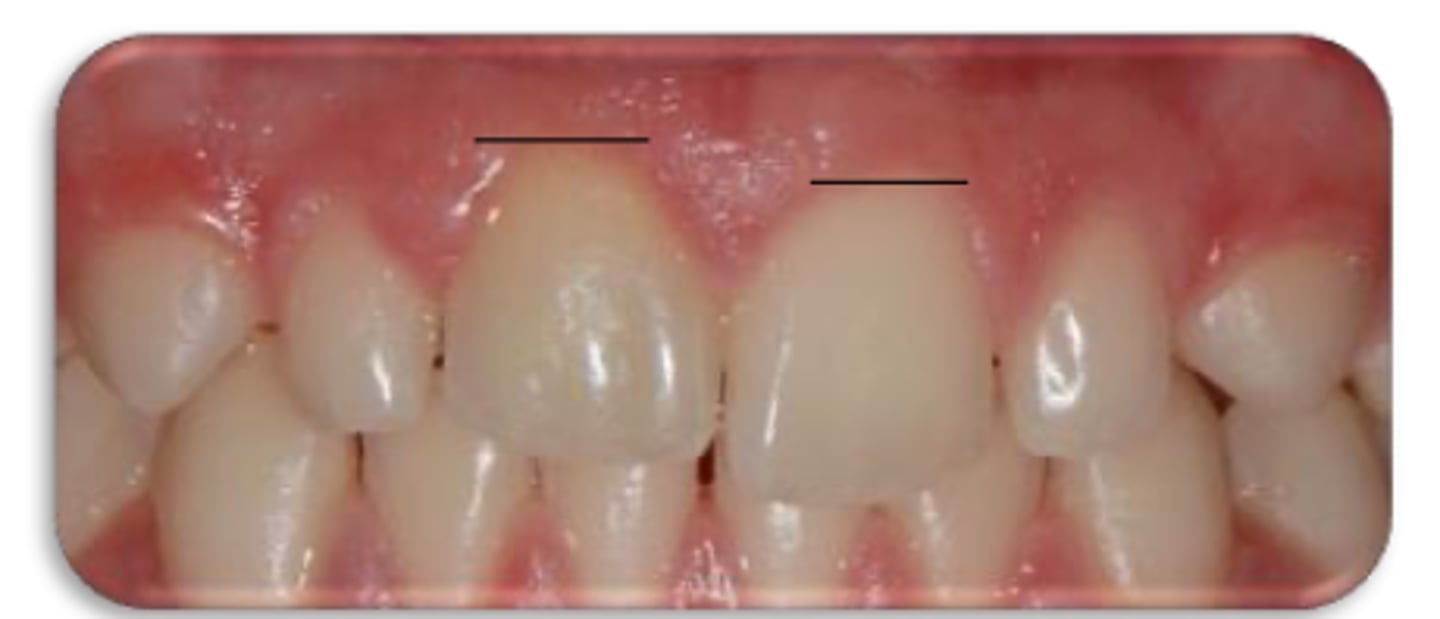

External cervical resorption (Invasive Cervical Resorption)

ID the type of resorption:

- Often asymptomatic until late stages, and may be misdiagnosed as caries

- Possible pink spot in the cervical aspect of the tooth, near gingival margin

- Often hemorrhagic on probing

- Feels hard and scratchy when probed (unlike subgingival caries which feels sticky)

A patient presents asymptomatic with a pink spot in the cervical aspect of the tooth, near the gingival margin. Upon probing, the pocket is hemorrhagic and feels hard/scratchy. What is the most likely diagnosis?